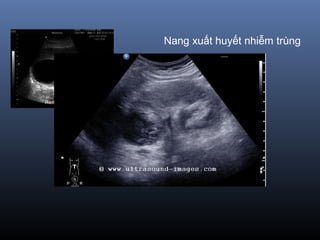

Nang xuất huyết nhiễm trùng

Nang xuất huyếtnhiễm trùng